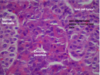

Islet Cell Tumor

Islet Cell Tumor

Insulinoma (Islet Cell Tumor)